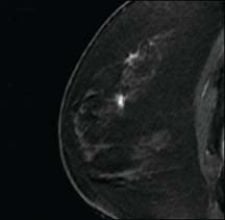

MRI-guided breast biopsy with the Suros ATEC system is viewed as one of the patient follow-up protoc

“Ultrasound is a good method to biopsy when you see something under MRI that is seen on ultrasound as well,” Lehman said. “It’s more comfortable for the patient and a less costly procedure. However, cancers seen on MRI can be completely invisible on targeted ultrasound, and I’ve seen many examples of where MRI has detected DCIS or small invasive cancers that were missed on ultrasound. This is not just my personal experience, but can also be found in published data in peer-reviewed literature.”

Lehman added that given the benefits of ultrasound-guided breast biopsy, targeted ultrasound is a reasonable initial approach to sample suspicious MRI lesions and may be particularly useful for masses larger than 5 mm. But the lack of ultrasound detection does not negate the need for biopsy of suspicious breast MRI lesions. And the guidelines for safe practice are no different for breast MRI than those used in mammography-ultrasound correlations.

Protocol at the University of Washington/Seattle Cancer Care Alliance dictates making the final recommendation at the time of the MRI interpretation. If the ultrasound is negative and the MRI lesion is probably benign, patient follow-up occurs after a short interval. However, if the ultrasound is negative and the MRI lesion is suspicious, an MRI-guided biopsy is recommended on the report. This removes the risk of the radiologist performing the negative ultrasound not understanding that the MRI lesion needs to be biopsied, regardless of the ultrasound findings.